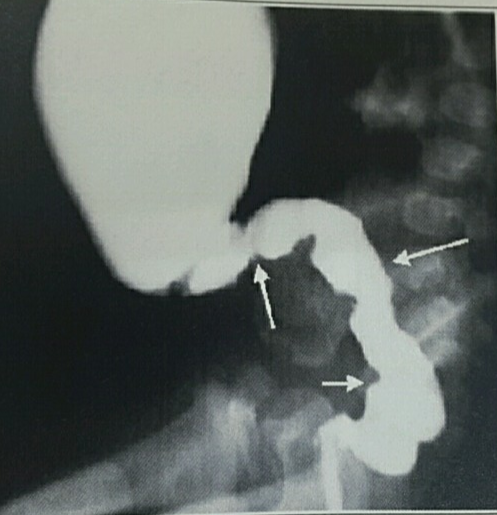

3) 대장 조영술

(1) 분명한 이행대(transition zone) 관찰

: 무신경절 부위는 연동이 없어서 좁아져 있고,

상부 결장은 폐쇄로 인한 확장 소견이 나타납니다.

(2) 24시간 후에도 조영제가 남아있는 것도

중요한 소견 중의 하나이다.

(3) 검사전 관장이나 직장수지 검사(DRE)는

이행대의 확인을 어렵게 하므로 시행하면 안됩니다.